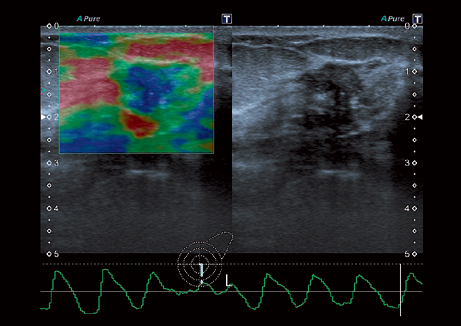

• Эластография

Компрессионная эластография:

Нет

Эластография сдвиговой волной/Эластометрия: